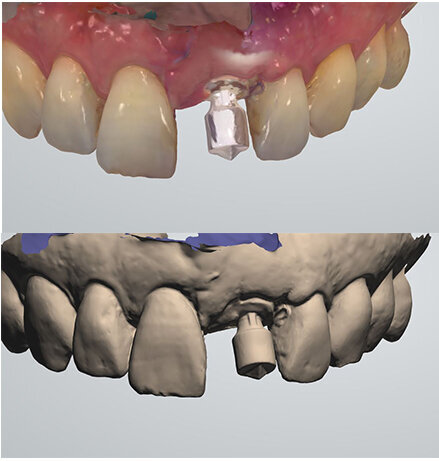

Intraoral scan

Eight days after surgery, the patient reported that healing was uneventful and the prosthodontist removed the stitches. It has become the author’s standard protocol to perform an intraoral scan for implant position in this same session (Figs. 24 & 25). The specific and unique PEEK healing abutment used has an internal circular channel and on one side, normally positioned on the buccal aspect, a vertical rectangular slot (Fig. 26). After removing the PTFE tape used to plug this area during surgery, a ScanPeg can be positioned inside the healing abutment. This allows for a unique scanning procedure without removing the healing abutment, thus avoiding disturbing healing tissue or dislocating recently placed biomaterials. The producer provides libraries for STL files of the five different anatomical shapes—wide incisor, narrow incisor, canine, premolar and molar—that determine the basic profile of the gingival tunnel during healing.